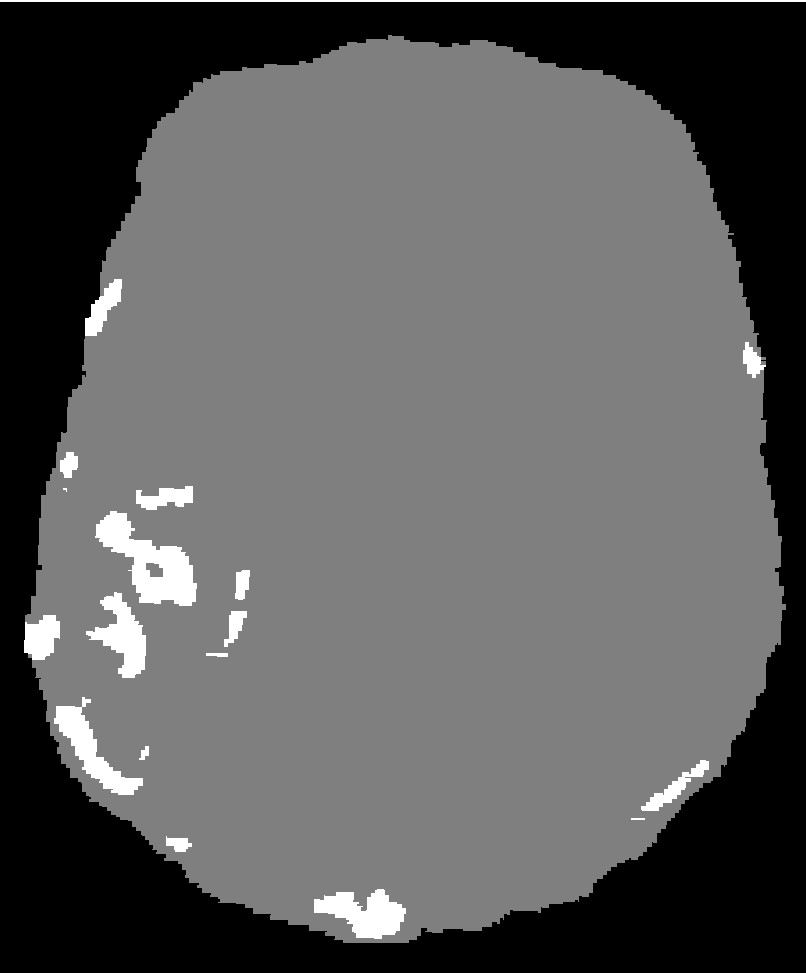

Figure 1: Brain MRI slice with AVM after skull stripping [5] LABEL:sub@DoeOne and after segmentation LABEL:sub@DoeTwo. LABEL:sub@DoeThree depicts a volume rendering of the segmented AVM. The segmented image has a spacing of 0.7×0.7×1.6mm30.70.71.6superscriptmm30.7\times 0.7\times 1.6\;\text{mm}^{3} and a size of 320×320×100voxels3320320100superscriptvoxels3320\times 320\times 100\;\text{voxels}^{3}.

The previous work [11, 12, 5] re-samples the segmented image to an isotropic unit-spaced image to avoid the transformation of the index to physical coordinates and vice versa. This approach is sufficient for fairly regular geometries and improves the speed of the mesh generation. However, in the case of complex data (i.e., AVM), image down-sampling can deteriorate the quality of the segmentation and may result in disconnected image regions or non-manifold connectivity (voxels that are connected to each other via an edge or a vertex). Figure 3 illustrates such an example. The presented method does not perform image down-sampling.

Figure 3: Brain Arteriovenous Malformation (AVM) segmentation, before and after down-sampling. The red circles indicate the problematic regions after down-sampling (i.e., disconnected voxels or non-manifold voxel connectivity).